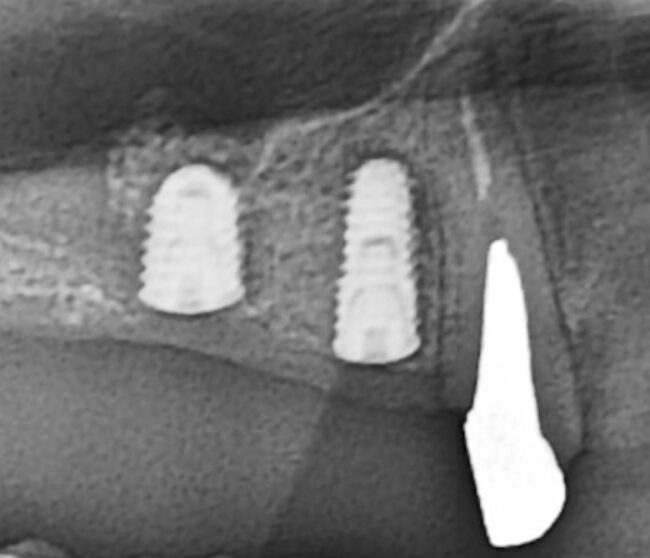

先日、インプラントのオペを行いました。骨が不十分なところに、ソケットリフトという骨造成のテクニックを併用してインプラントを2本埋入しました。

患者様曰く、以前に他院でインプラントができないと言われたそうですが、骨造成を併用すれば問題なくインプラントのオペができました。

インプラントで悩んでいる方がおられましたら、ぜひ当院にてご相談ください。